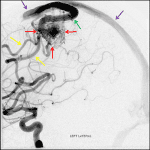

- Tangle of vessels centered in the left precentral gyrus at the location of the motor hand knob measuring 2 x 1.5 cm with feeding arterial branches from the superior and inferior divisions of the left MCA and superficial venous drainage via an engorged left cortical vein to the superior sagittal sinus

Arteriovenous malformation centered in the left precentral gyrus at the location of the motor hand knob measuring 2 x 1.5 cm with feeding arterial branches from the superior and inferior divisions of the left MCA and superficial venous drainage via an engorged left cortical vein to the superior sagittal sinus. No evidence of intranidal aneurysm or deep venous drainage.